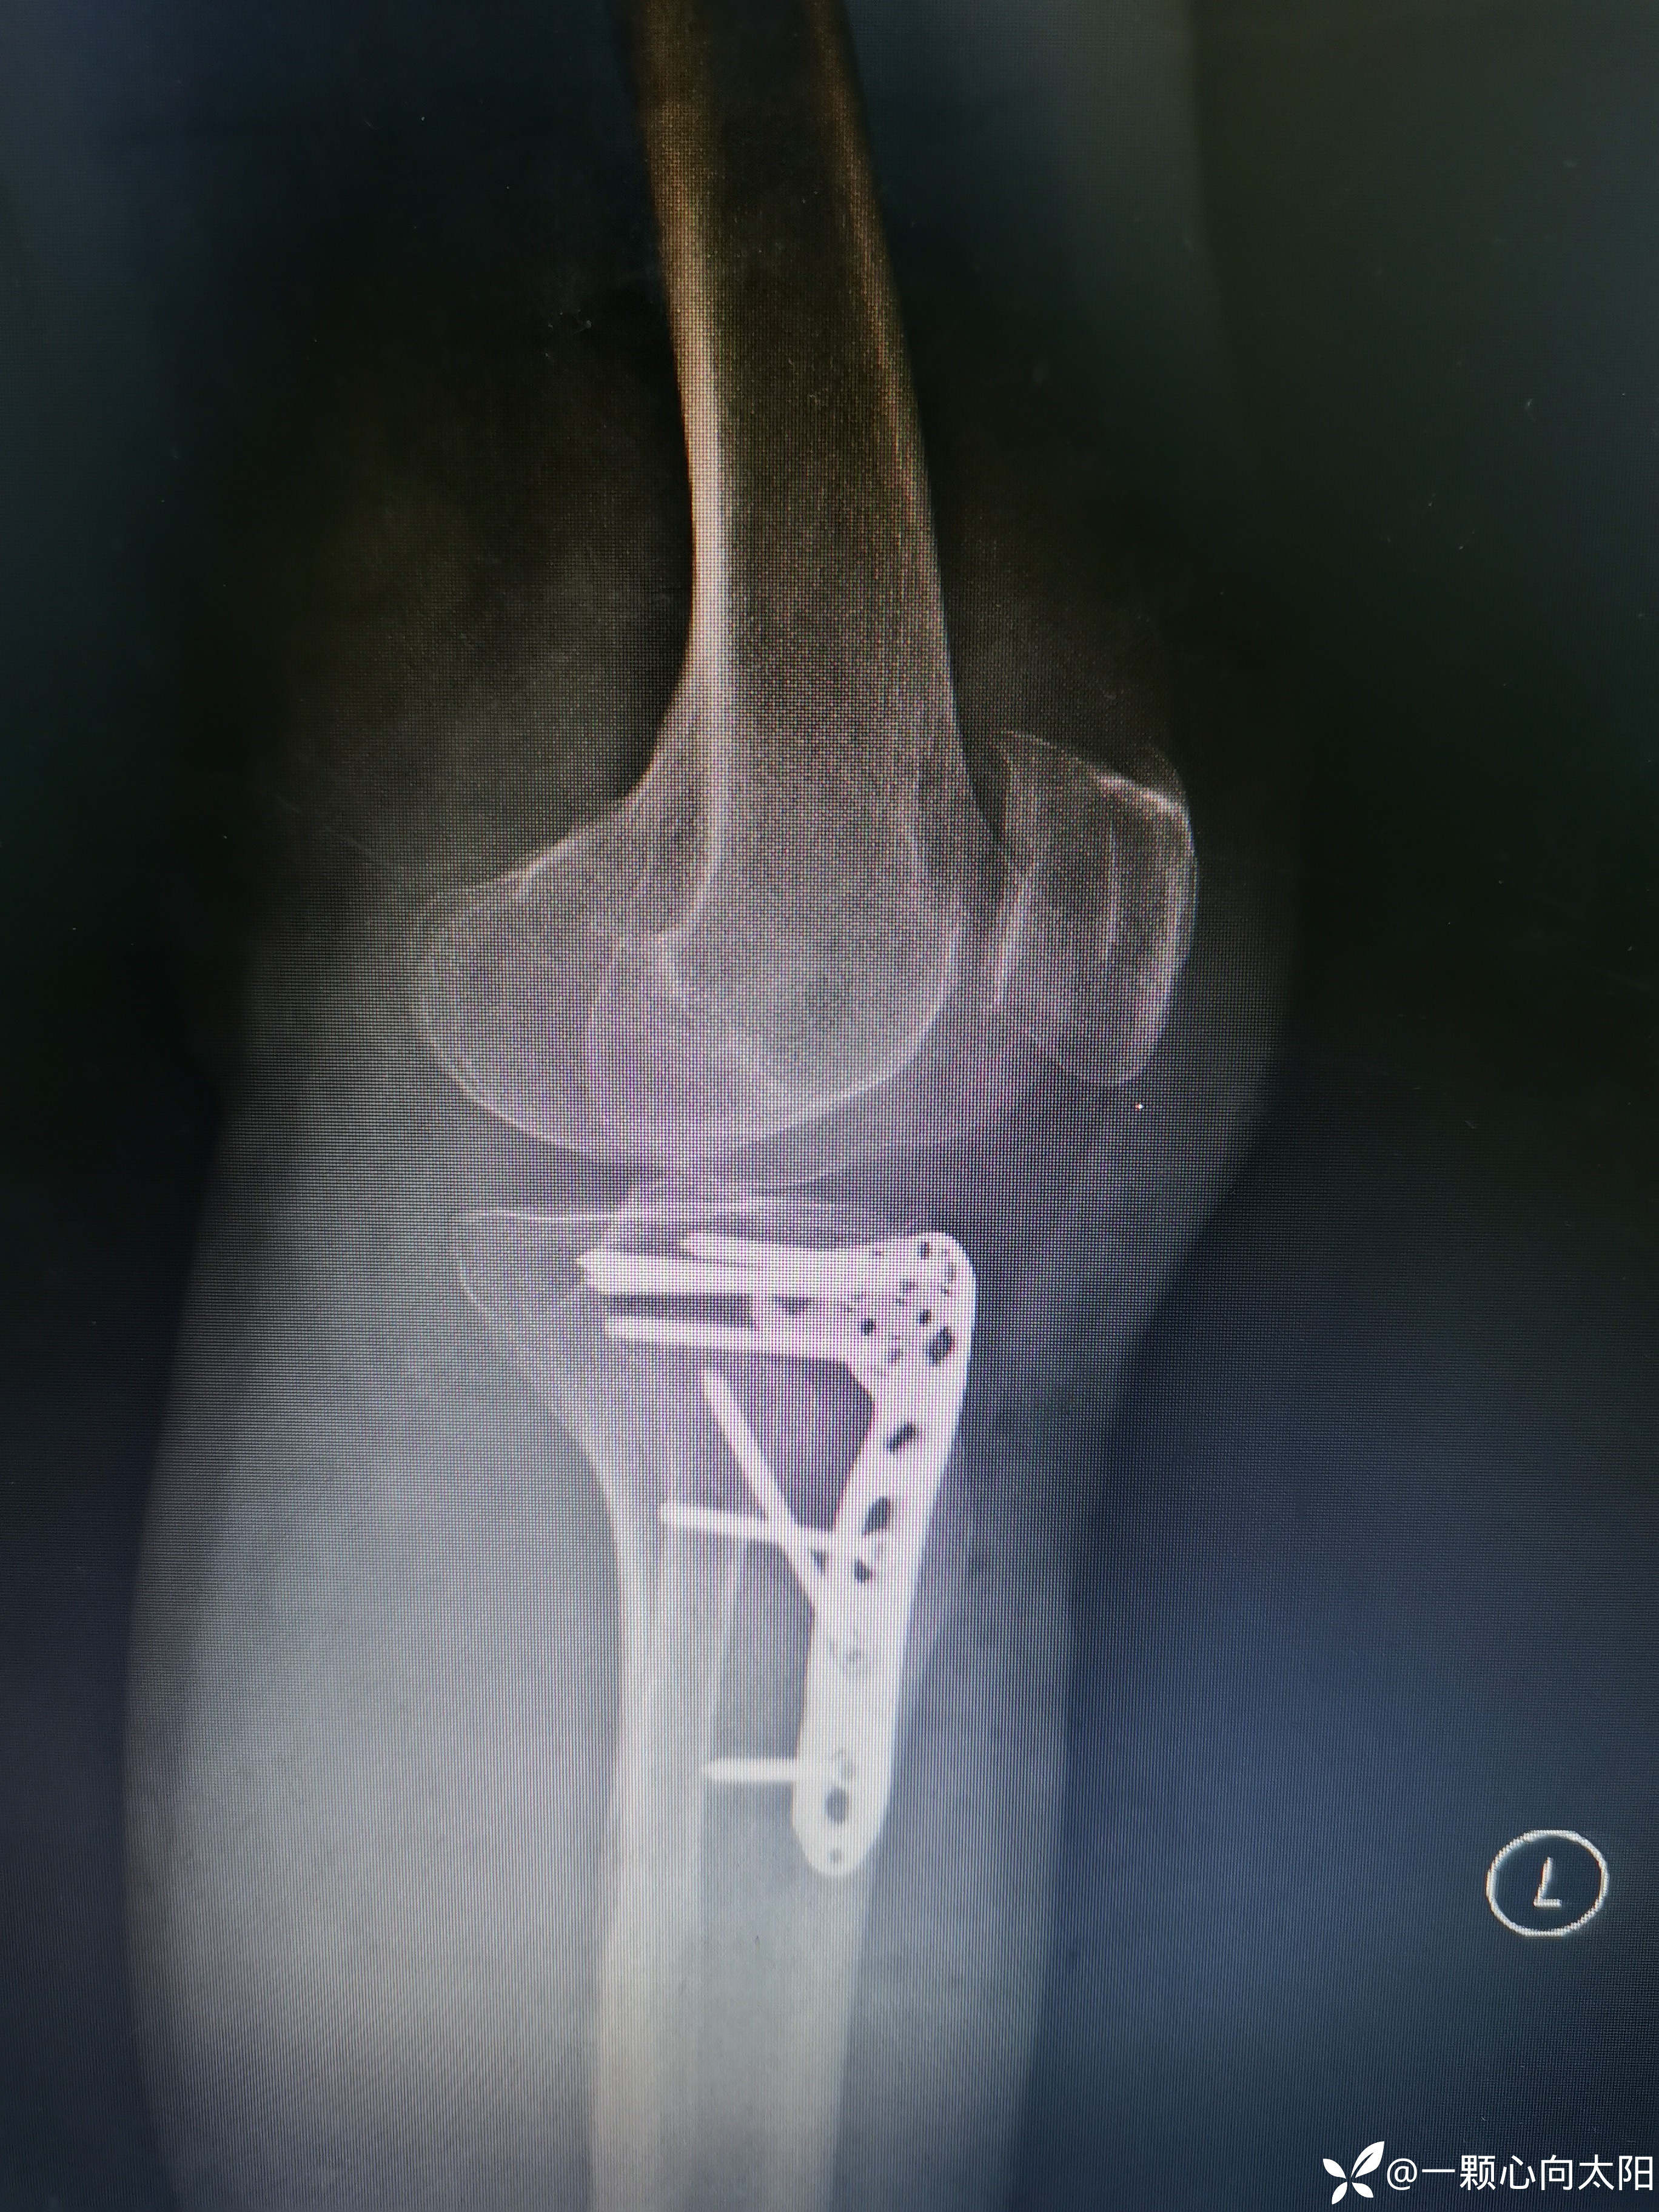

69岁,女性患者,以“外伤致左膝关节疼痛伴活动受限3小时”为主诉入院。

完善术前检查排除手术禁忌后行切开复位内固定术